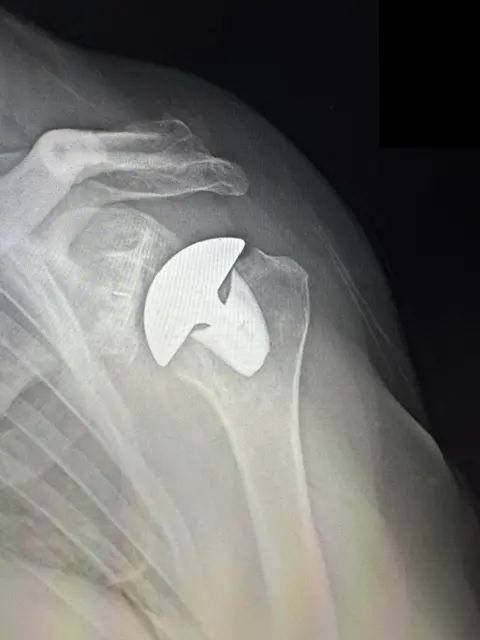

Total Shoulder Replacement

Total shoulder replacement is a surgical procedure that reconstructs the damaged joint using prosthetic components that restore the shoulder’s natural anatomy.